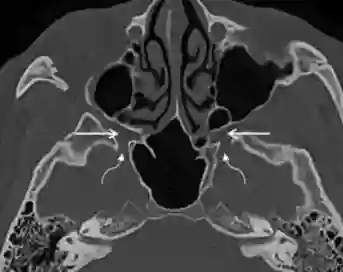

Fossa pterygopalatina im CT

Darstellung der Fossa pterygopalatina (gerader Pfeil), welche über das Foramen rotundum (gebogener Pfeil) mit der mittleren Schädelgrube kommuniziert im axialen CT. Abbildung adaptiert von Tashi et al. 2016.